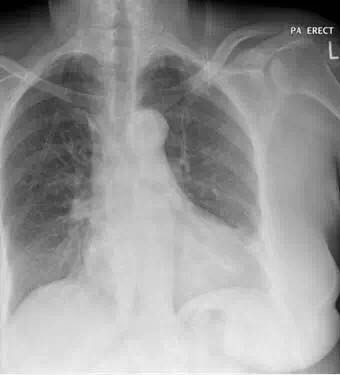

窦性心动过速,心率100次/分。无其它异常。 胸片:

患者胸片显示左基底不透明,患者有呼吸急促加重,胸膜炎性胸痛与此诊断相符。白细胞数量增加,CRP和胸片符合肺炎的诊断。患者胸片也符合肺栓塞诊断。d-二聚体阳性符合肺栓塞诊断,同时d-二聚体升高也可见于很多感染和炎症过程。尽管患者有哮喘史,但目前没有支气管痉挛的证据。胸片不符合肺水肿诊断,同时缺少其他临床证据。胸片未出现气胸症状。患者没有任何免疫功能减弱症状或病史提示有肺孢子虫性肺炎感染风险。 入院继续完善CTPA结果: